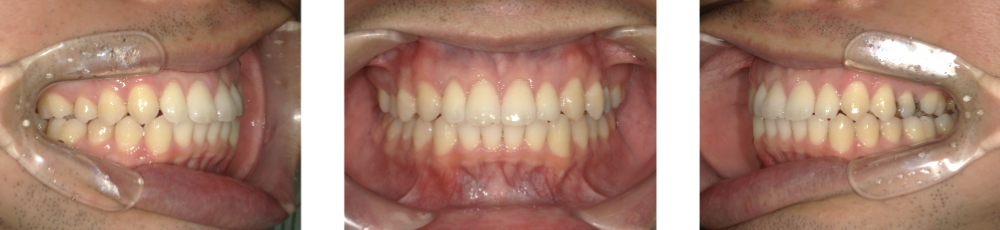

After Photo

After

上の前歯に隙間があるため、前歯を後退させながら、隙間を閉じた。

この時、上下の前歯が強く干渉すると再度隙間が空いてくるため、上下前歯の咬合が強くならないように配列した。

矯正での歯の移動のリスクとして歯根吸収、歯肉退縮、歯髄怪死が考えられます。

保定装置の装置を怠ると隙間が生じてくる可能性があります。